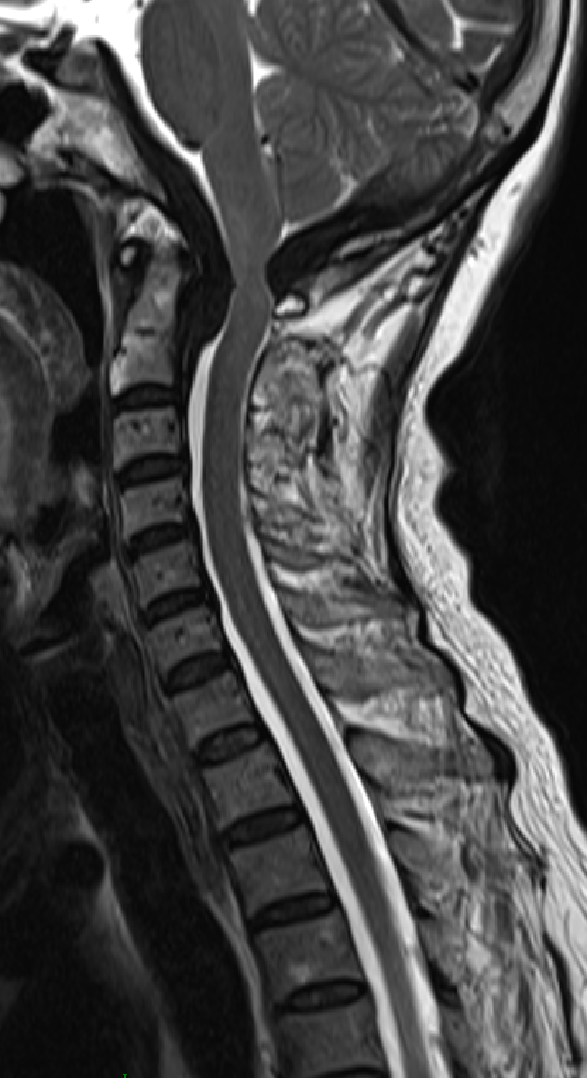

2015-4-1 MRI

2015-4-1

2014-12-13

2013-8-2